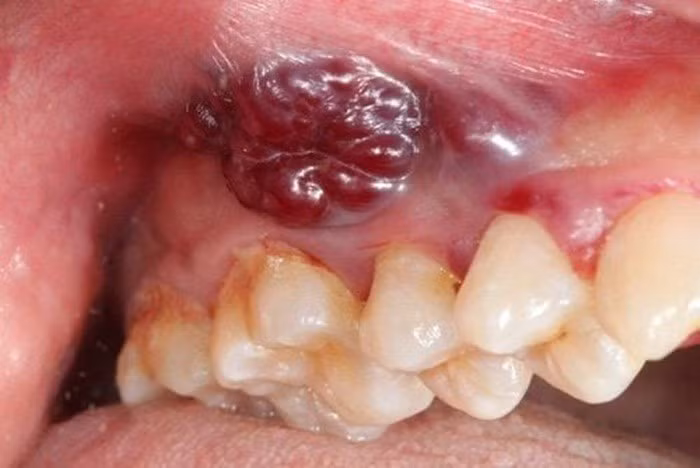

Vùng tổn thương nhô lên kèm loét và chảy máu là dấu hiệu của ung thư khoang miệng/ (Ảnh minh hoạ/Internet)

Phát hiện sớm ung thư khoang miệng có thể thực hiện qua việc thăm khám lâm sàng các tổn thương nghi ngờ. Vì vậy, việc tự theo dõi và nhận biết nguy cơ ung thư khoang miệng là vô cùng cần thiết. Chúng ta có thể nhận biết bản thân có nguy cơ mắc bệnh hay không bằng cách phát hiện các dấu hiệu sớm của ung thư khoang miệng qua các dấu hiệu cảnh báo theo các bác sĩ như sau:

U nhú màu trắng, thường xuất hiện tại lợi hàm hoặc niêm mạc má và hầu hết không có triệu chứng; Chấm trắng xuất hiện trên nền niêm mạc bình thường với bề mặt gồ ghề và bờ viền không đều; Tổn thương niêm mạc gây ra bởi răng giả hoặc bờ răng sắc nhọn, không lành sau 2 tuần; Tổn thương dạng cục cứng dưới niêm mạc với bờ viền không rõ, không đau và phát triển to ra từ từ.

Niêm mạc trên bề mặt bình thường; Tổn thương niêm mạc không rõ nguyên nhân và không lành sau 2 tuần; Tổn thương không lành sau nhổ răng, sưng đỏ, dễ chảy máu khi chạm vào tổn thương. Một vùng niêm mạc khoang miệng trở nên đỏ và gây đau rát, khó lành; Xuất hiện đau vùng khoang miệng không rõ nguyên nhân, đau ngày càng trầm trọng hơn.